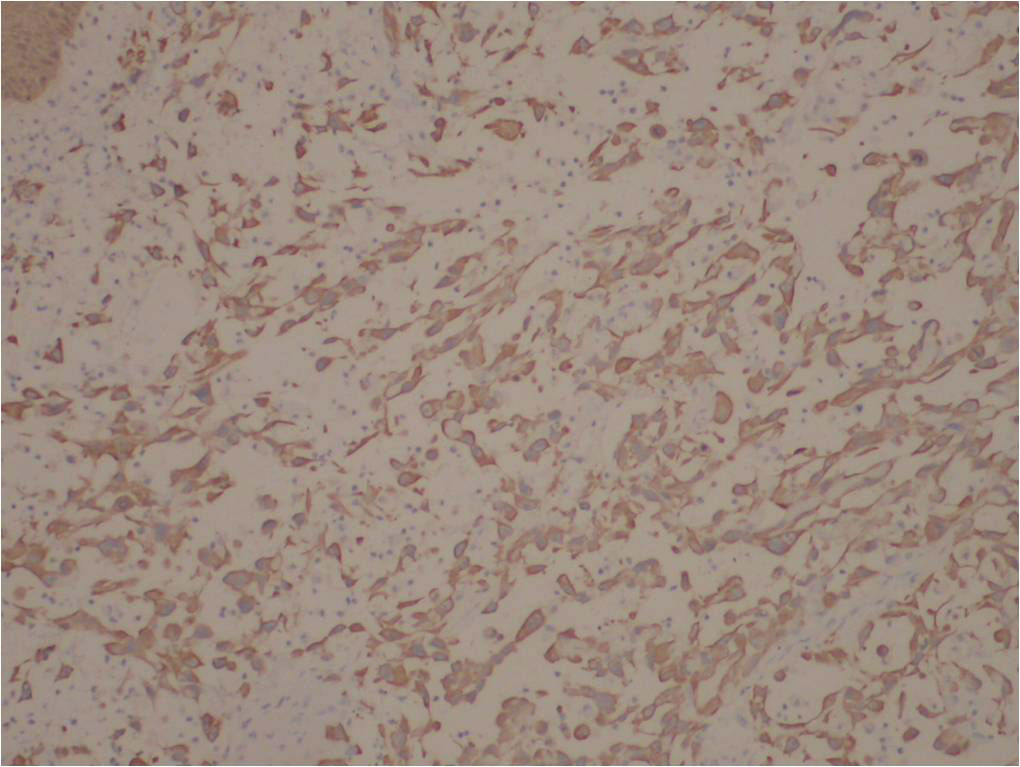

免疫组化结果:

阳性:  CKVimCK5/6CK14

阴性:  MyoD1MyogeninDesminSMAEMACD34HMB45CK8/18CEA

特染:  AB-PAS(-)